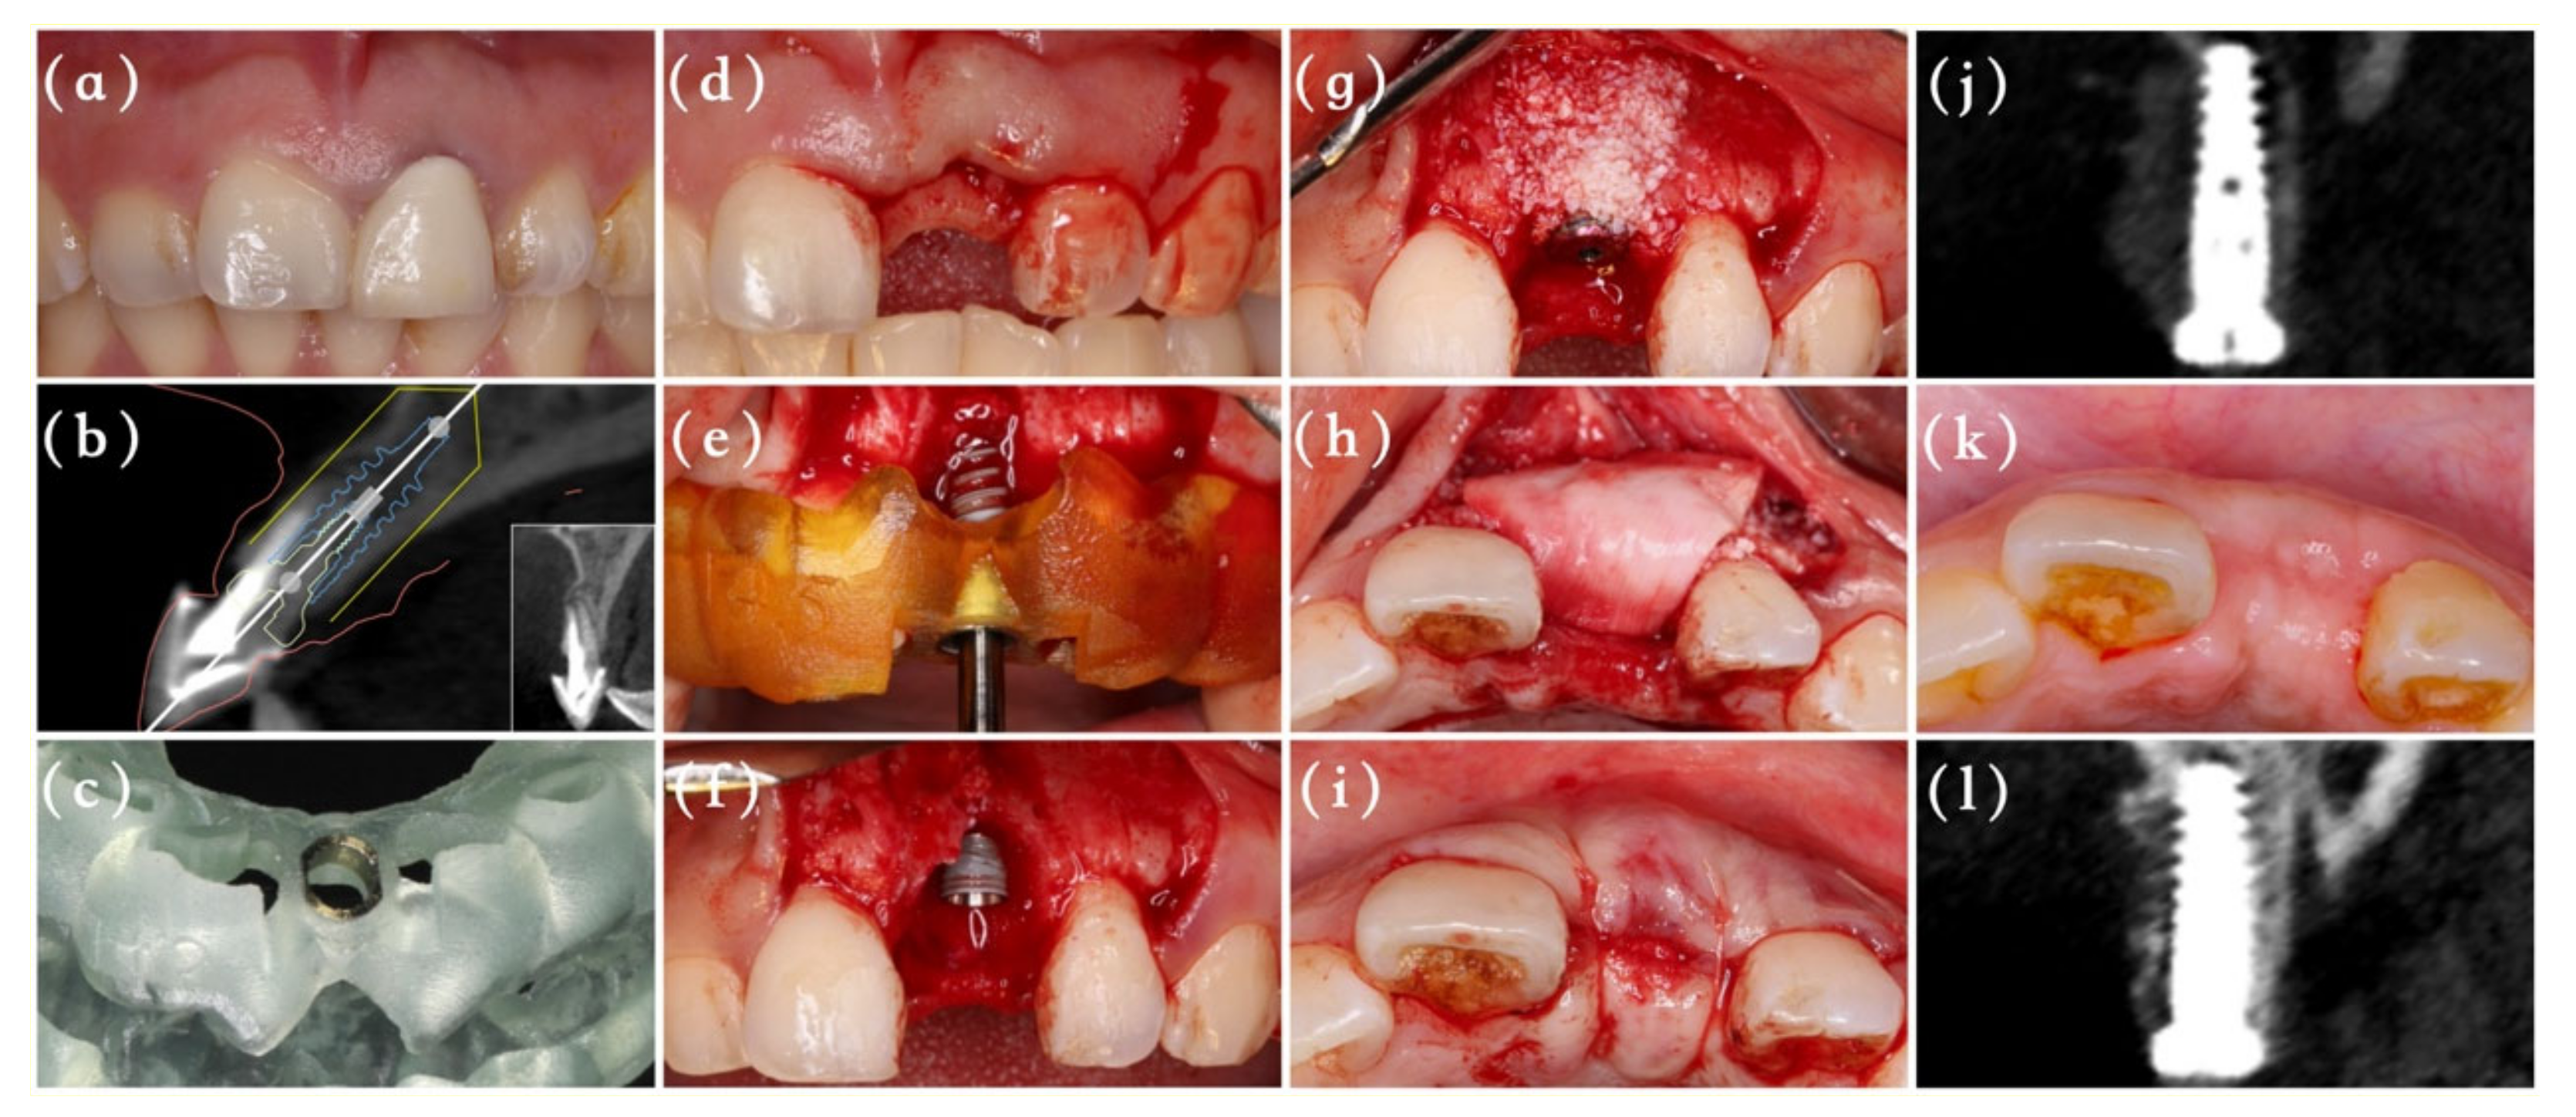

2.2. Surgical Procedures